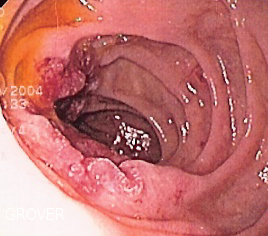

6. 1. 1. 구강암, 식도암, 인두암, 후두암

서울대학교병원에서 2022년에 450만 명 이상을 대상으로 7년 이상 수행한 연구는 알코올 섭취와 암 발생 위험의 관계를 조사했다.[244] 연구 결과, 알코올 섭취량을 늘린 사람들은 동일 수준을 유지한 사람들보다 암 발생 위험이 높았다. 특히, 음주를 하지 않던 사람이 가볍거나 적당한 음주를 시작한 경우에도 위험이 증가했다.알코올 섭취는 섭취량과 관계없이 구강암, 식도암, 인두암, 후두암 발병의 위험 요인이다. 미국 국립암연구소는 알코올 섭취가 남성과 여성 모두에게 입, 식도, 두경부, 후두암 발병 위험을 높이며, 담배와 알코올을 함께 사용하면 각각 단독으로 사용하는 것보다 구강, 두경부, 식도암 발병 가능성이 더 높아진다고 밝혔다.[246]

국제 인두암 역학 연구 연합체(INHANCE)는 이 문제에 관한 메타연구를 진행했다.[247] 후두암과 음료 유형의 관계를 조사한 연구에서는 와인 섭취가 후두암 위험과 가장 관련이 깊은 음료임을 밝혔다.[248]

1966년부터 2006년까지 발표된 역학 문헌 리뷰 연구에서는 알코올 중단 후 식도암 발병 위험이 감소하며, 20년 이상 지나면 알코올을 전혀 마시지 않은 사람들과 유사한 수준으로 나타난다고 결론 내렸다.[249][250]

한 연구에 따르면, 매일 정기적으로 술을 마시면 구강암 및 인두암 발병률이 1000명당 1명, 식도암 및 후두암 발병률이 1000명당 0.7명 증가한다.[245]

2008년 연구에서는 알코올 분해 생성물인 아세트알데히드가 구강암과 관련 있을 수 있다고 제시했다.[251][252]